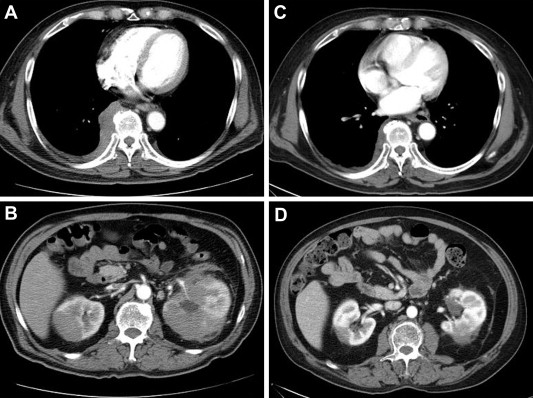

The patient first received a thoracoscopic biopsy, and a pathologic examination reported an inflammatory pseudotumor, suggestive of IgG4-related sclerosing disease. After thoracoscopic biopsy, his condition still did not improve and laboratory tests revealed eosinophilia (7.9%), a low testosterone level (<0.008 ng/ml; reference range, 1.66–8.11 ng/ml) and primary hypoadrenalism with a low cortisol level (0.65 μg/dl before 10 am; reference range, 4.46–22.69 μg/dl) and an elevated adrenocorticotropic hormone (ACTH) level (56.1 pg/ml; reference range, <46 pg/ml), but other pituitary hormones were within the normal range. The brain magnetic resonance imaging (MRI) demonstrated a 2.4-cm, well-defined mass in the sella turcica, showing isointense on a T1- and T2-weighted image with strong enhancement after injection of the contrast medium (Fig. 2). No residual normal pituitary tissue of the posterior lobe was noted. The mass lesion extended upward and compressed the optic chiasm. Macroadenoma was initially suspected. Then, he commenced glucocorticoid replacement therapy and received transsphenoidal removal of the infundibulum mass.

Well-defined mass in the sella turcica with strong enhancement after the injection of contrast medium.